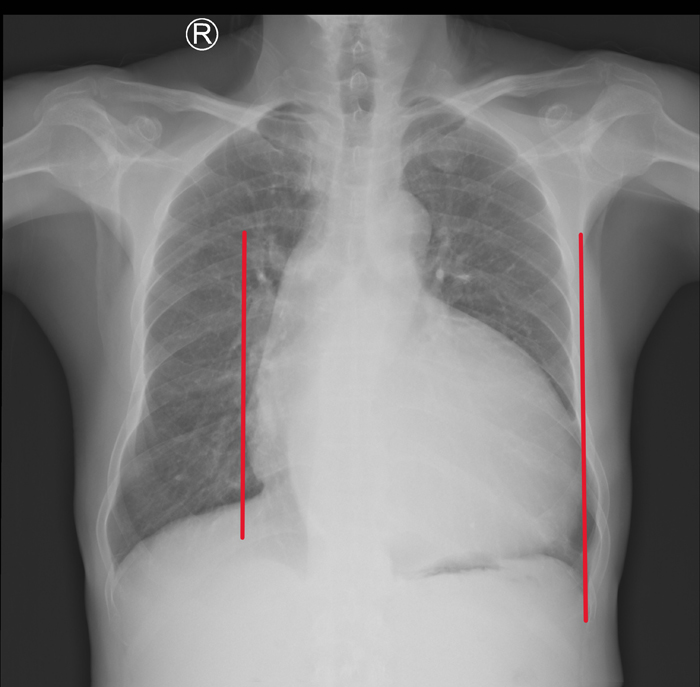

近日,潞河医院心脏外科团队成功为一名左心室直径达105毫米(远超正常上限55毫米)、心胸比高达0.75(正常比为0.5)的终末期心脏瓣膜病患者实施了高难度手术。

五个月前,李先生莫名出现夜间无法平卧、端坐呼吸的严重心衰症状,却误以为是感冒没有及时就医。直到胸闷加剧、体力断崖式下降才来到潞河医院就诊。入院检查显示:脑钠肽(一种心衰标志物)高达1820皮克/毫升(正常值<100皮克/毫升),心脏超声提示:左心室显著扩大至105毫米,主动脉瓣及二尖瓣重度反流,左心功能严重受损,随时面临猝死风险。巨大心脏挤压胸腔,双肺淤血,随时可能引发多器官衰竭。面对这颗“超载”的心脏,心脏外科主任杨海平带领团队与重症监护室、麻醉科等相关科室经多学科论证一致认为:单纯药物已无法逆转心衰,但传统心脏移植面临供体短缺困境,于是果断制定了“主动脉瓣+二尖瓣机械瓣置换+三尖瓣成形”的复合术式,术中备左室辅助装置,手术风险极高,难点环环相扣:心脏复跳难:巨大左室心肌收缩力极弱,术后复跳风险极高;操作空间小:扩大的心腔挤压手术视野,瓣膜植入精度要求严苛;循环崩溃风险:术中室颤概率激增,需体外循环团队全程护航。